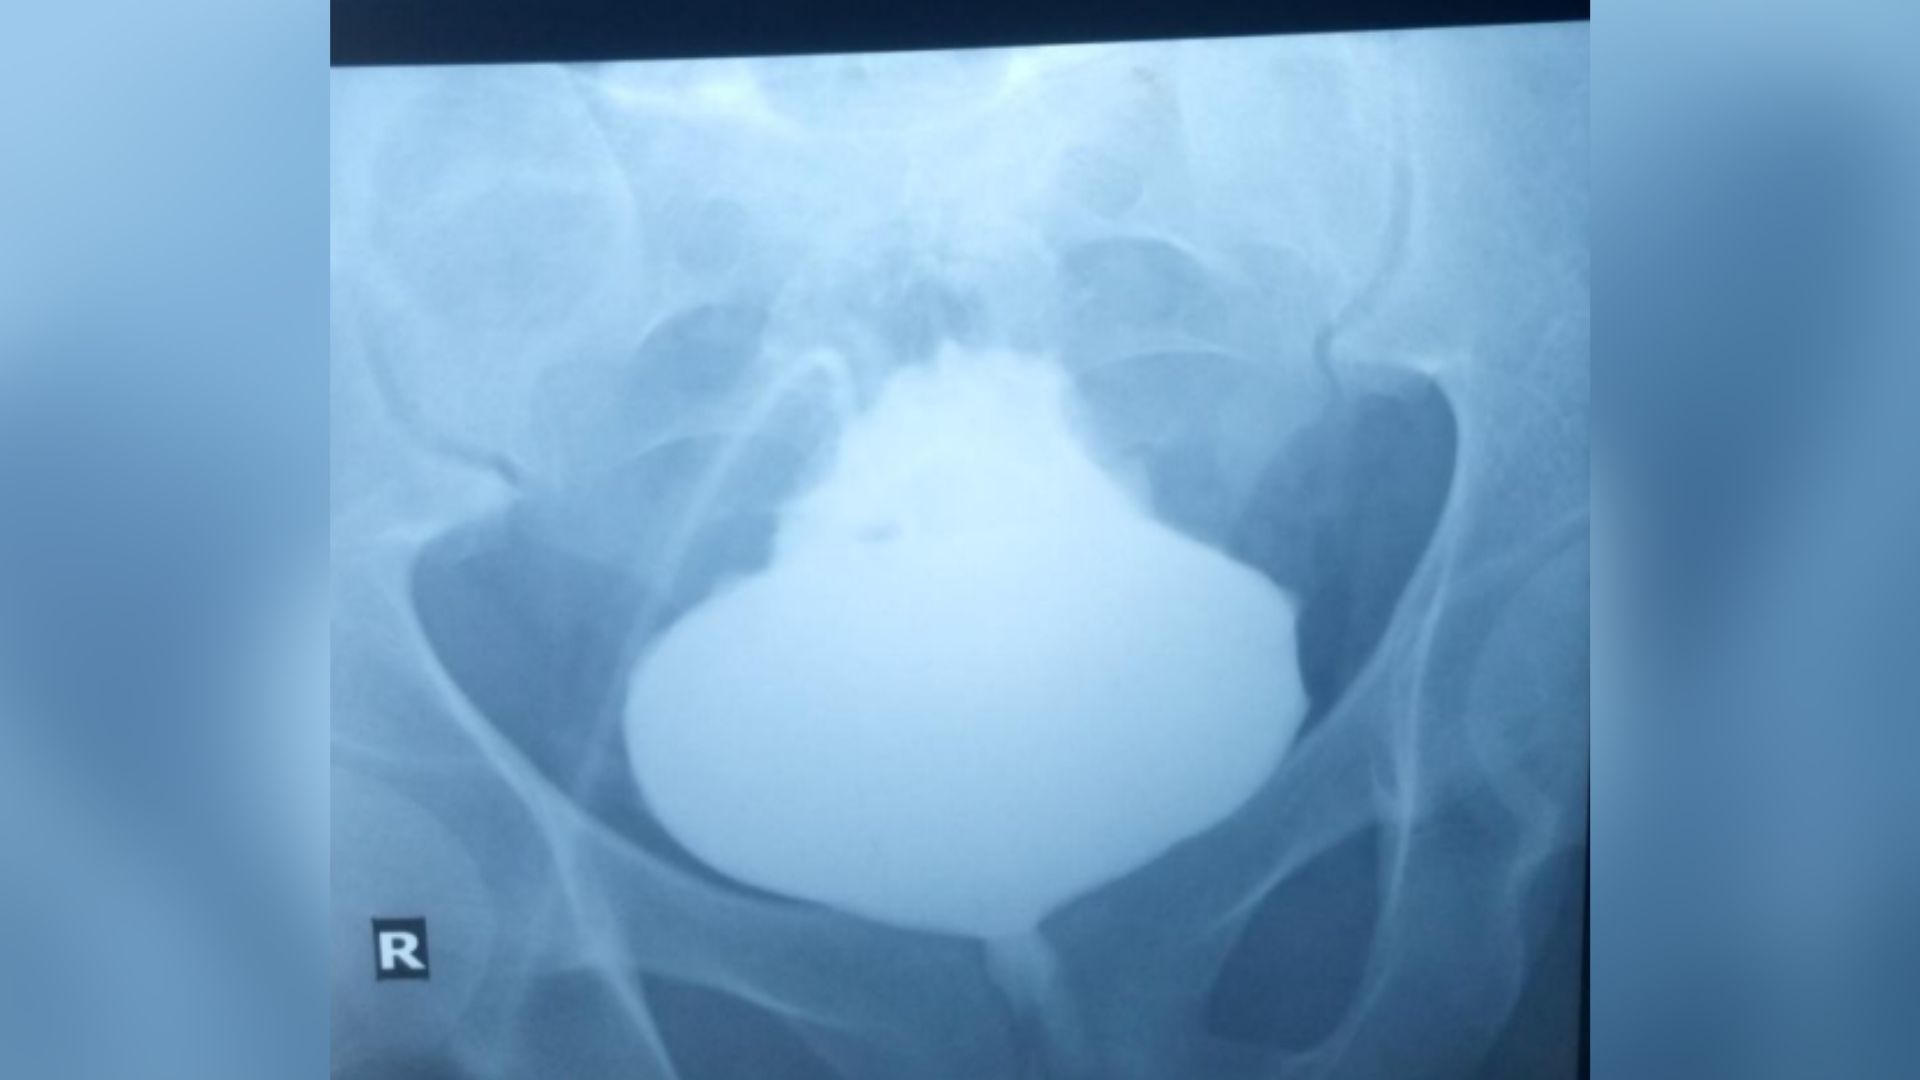

Que s’est-il passé ensuite : Lors d’un examen physique à l’hôpital, les mains de l’homme ont été immergées dans l’eau pendant 10 minutes, ce qui a immédiatement rendu le dessus de ses mains, ses doigts et ses poignets rouges, squameux et ridés avec des lésions blanches. Notamment, les « rides excessives » et les bosses se terminaient par une ligne droite sur les côtés de ses mains, laissant ses paumes intactes.

Les médecins ont effectué des biopsies des bosses blanches sur sa main droite, qui ont révélé que les canaux sudoripares de la couche supérieure de la peau se sont élargis et contenait plus de glandes sudoripares que la normale. Les résultats ont également montré qu’il avait hyperkératosece qui signifie que son corps produisait trop de protéine kératine, provoquant un épaississement de la couche externe de la peau.

Le diagnostic : Les médecins ont diagnostiqué chez le patient une maladie appelée acrokératodermie seringue aquagénique (AAS) en fonction de l’apparition de ses symptômes à la clinique et des résultats de la biopsie. Cependant, dans presque tous les autres cas, elle affecte la paume des mains et non le dos des mains ou des doigts.